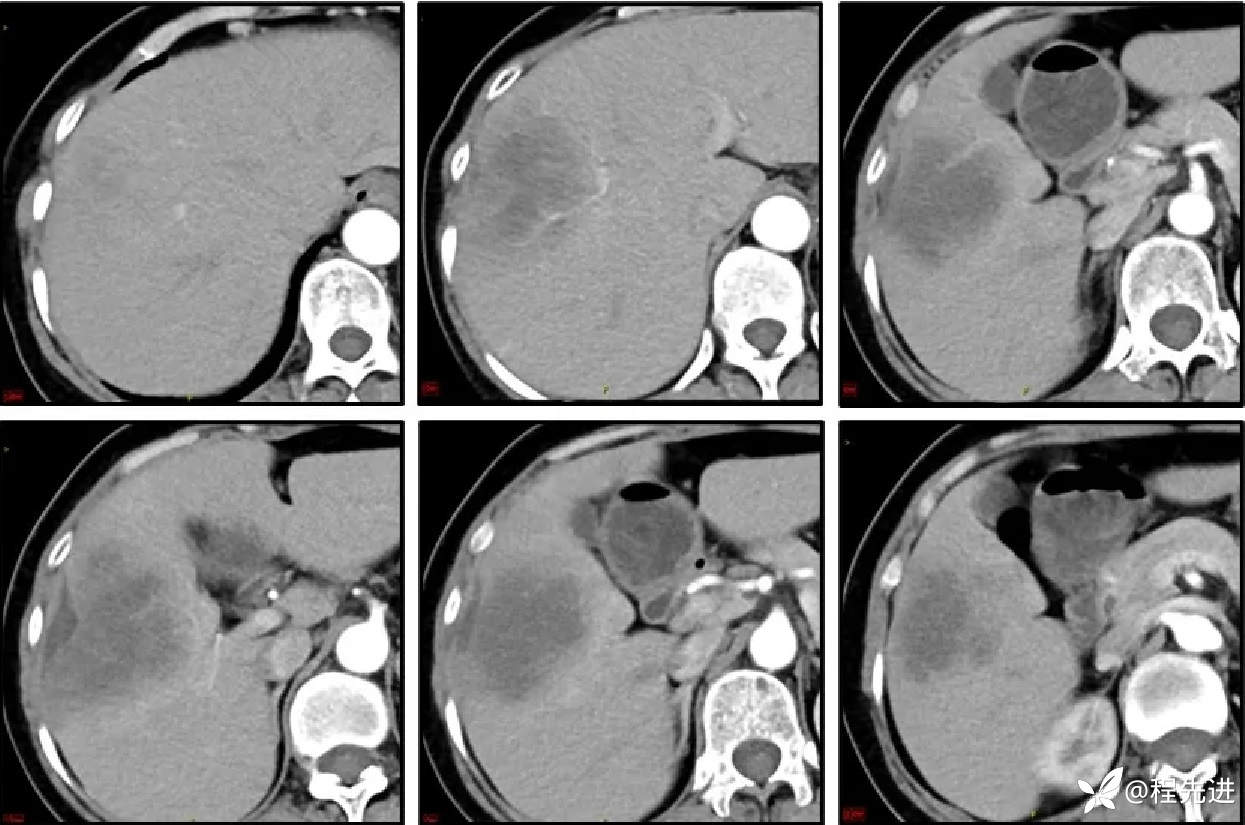

CT增强,3期: